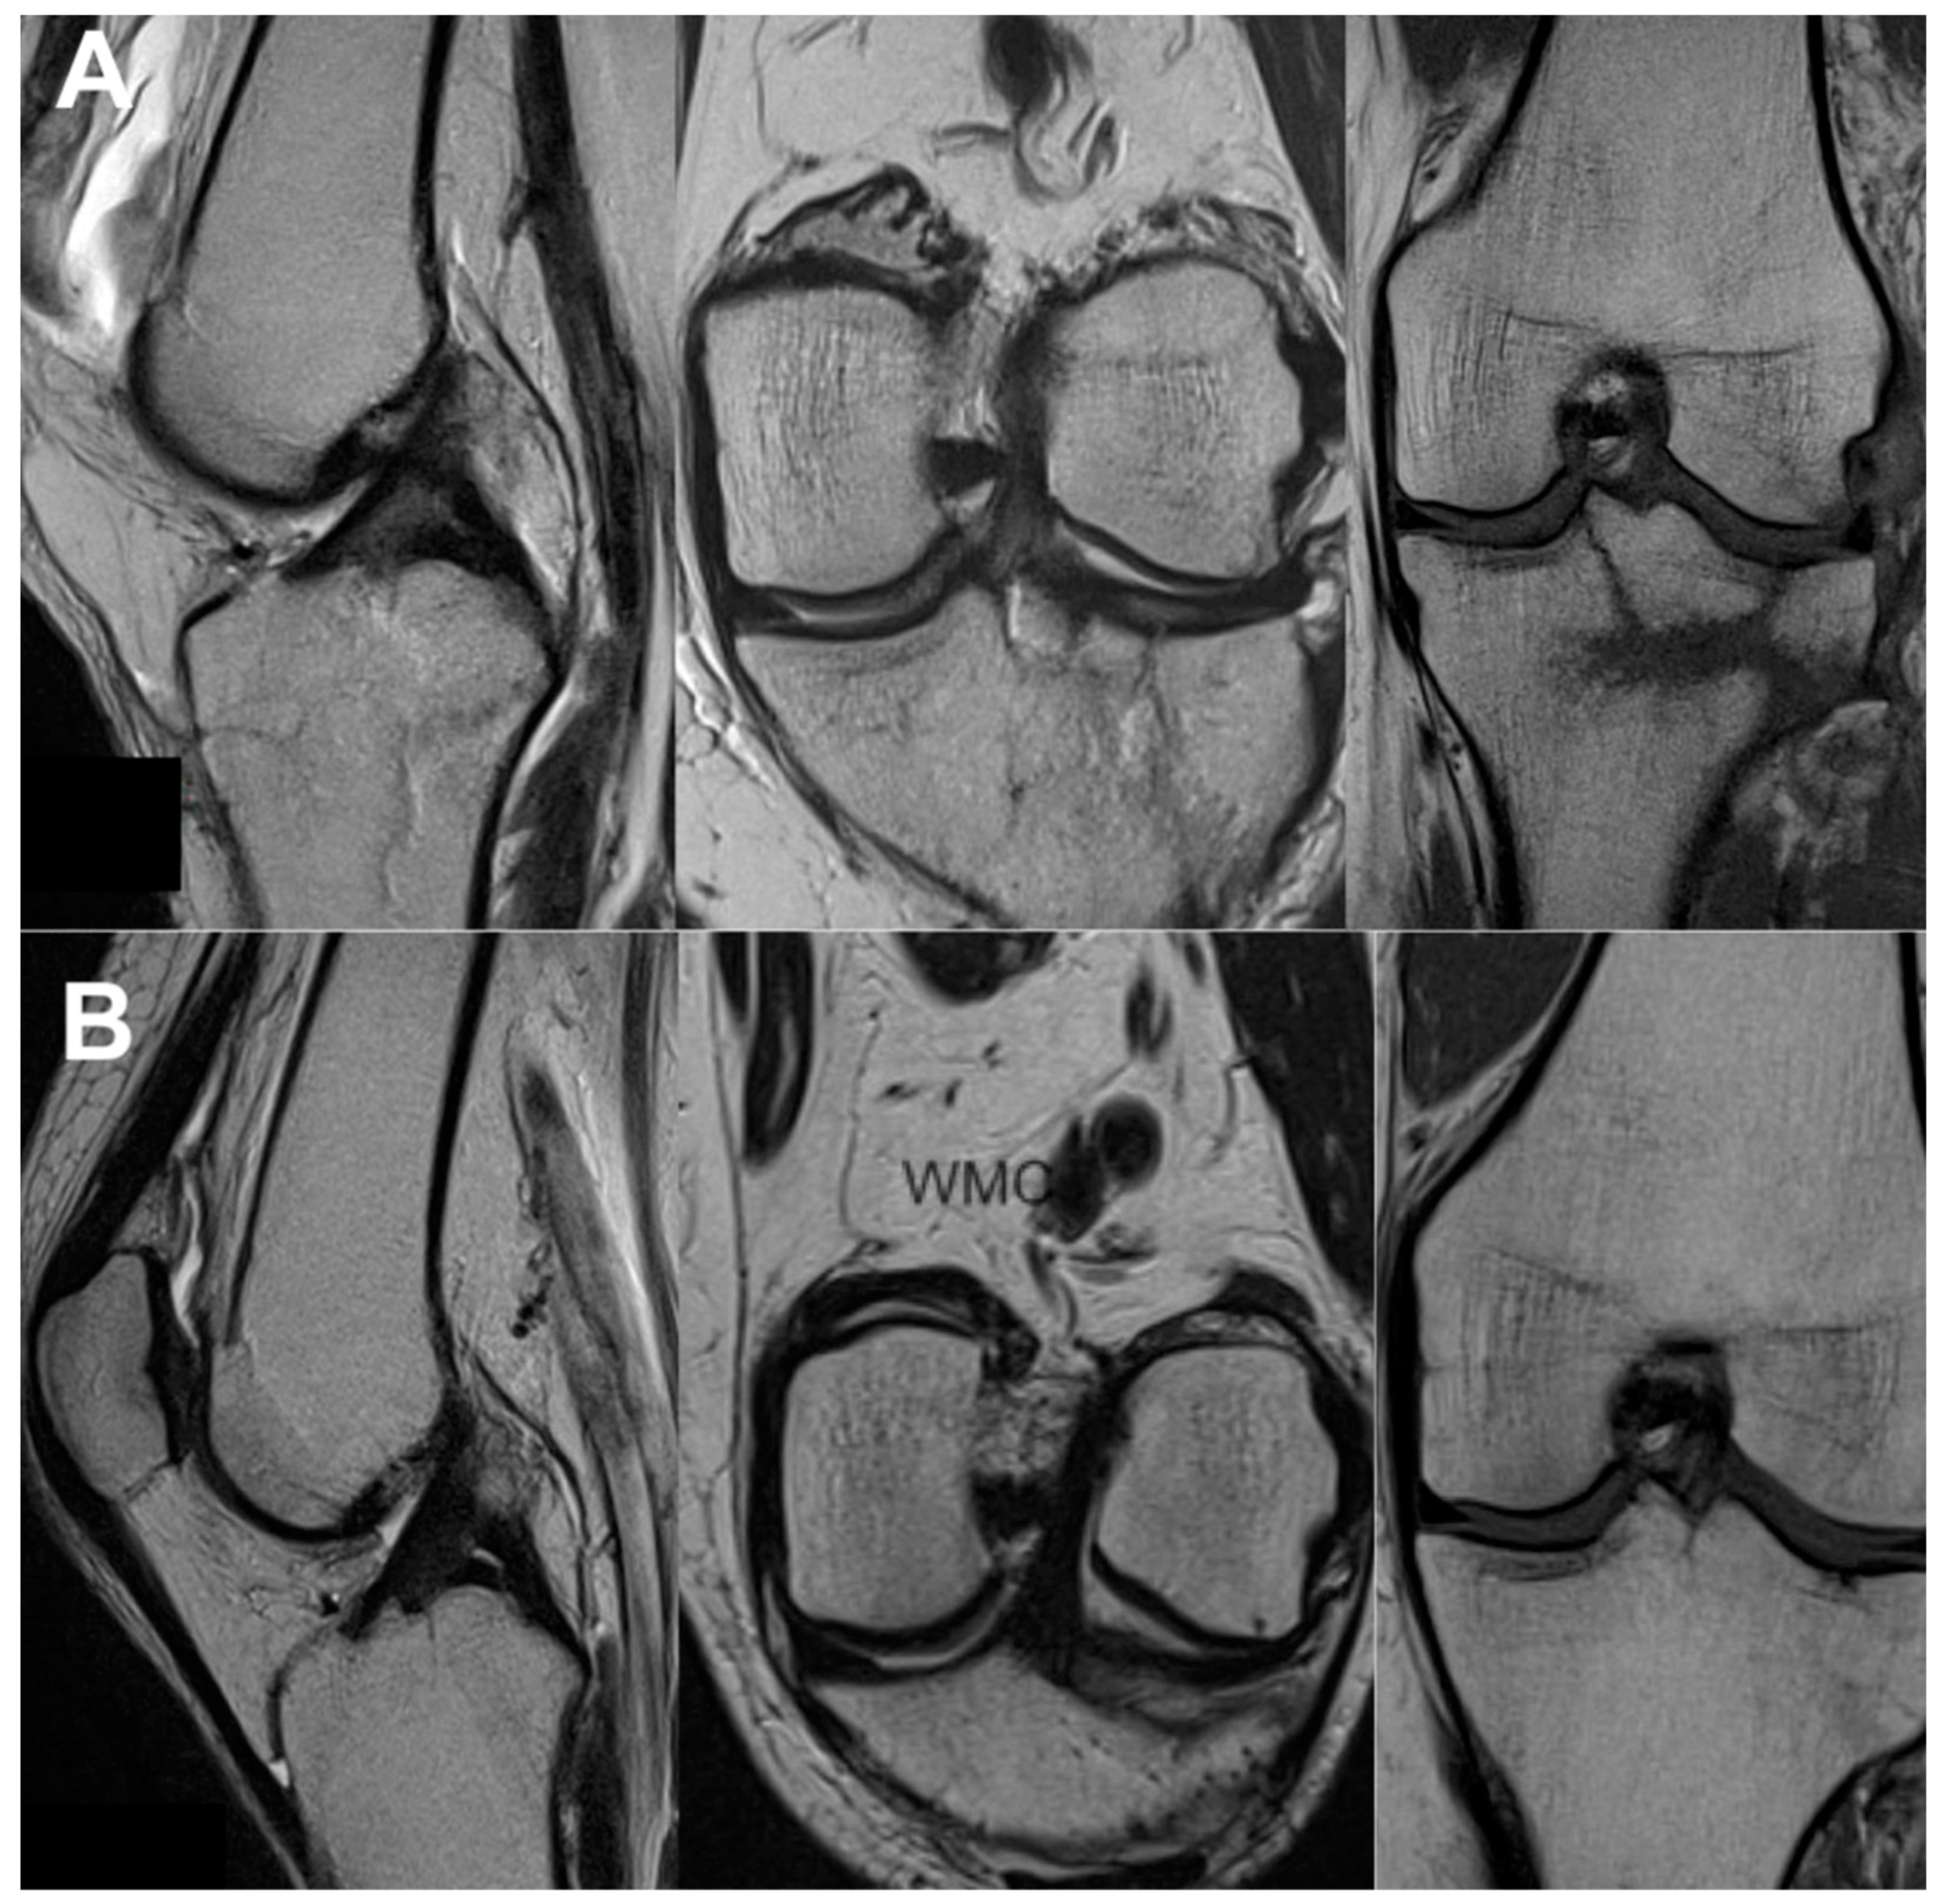

3.3. Imaging Analysis